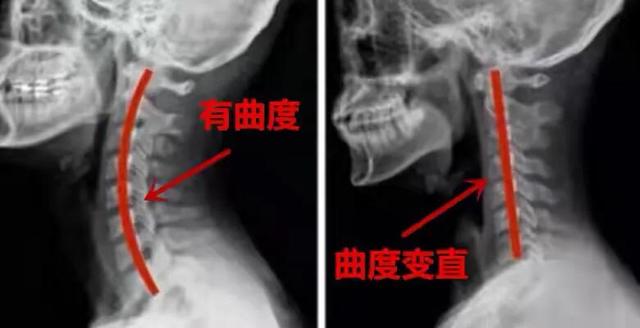

実際、聞こえてくるクリック音は、頸椎の小さな関節がバネでリセットされる音で、頸椎が極めて不安定な状態にあることも示しています。私たちの頸椎は、靭帯や関節包の補強に囲まれた、噛み合わせの部分なので、一般的な状況としては、頸椎の活動はうるさくありません。

しかし、低頭の長い時間、または年齢とともに、頸椎の小さな関節の周りの靭帯、関節包が緩くなり、関節のずれがあるでしょうし、首を移動すると、クリック音が鳴ります。このような頸椎は、枕の落下を繰り返し、関節面の過形成や硬化、さらには神経根や血管の刺激や圧迫を引き起こし、頸椎症に発展しやすい。

首のクリックやいくつかの提案を与えるために:まず、通常、頸椎に過度の負荷を避けるために、低い頭を減らすために勉強や仕事、第二は、適切な枕の高さで寝ることであり、パッドの位置は、頸椎の正常な湾曲を維持するために、後頭部ではなく、首でなければなりません、第三は、頸椎の安定性を高めるために、運動の機能を強化するために首のコアの筋肉群を強化することである。